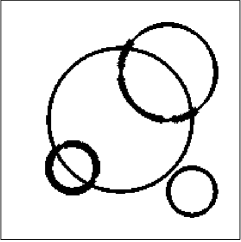

The data (see Figures 1 and 2) was generated in the diffusion model (1.2) using self-written (linear-basis) finite element code in MATLAB. For both examples, we took and used a uniform boundary condition . The simulated data were generated on a -grid and then down-sampled (by averaging) to to avoid inverse crime. After that, Gaussian noise with different intensities (standard deviations of and of the average signal value ) was added to the data.